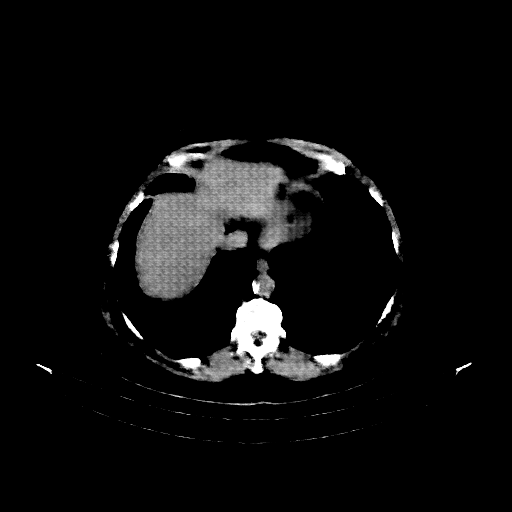

Reconstructed NATIVE CT scan (cycle consistency)

Full window (WL 1023.5, WW 4095 β†’ Low βˆ’1024, High +3071)

Actual HU range: [-1024.0, 783.0]